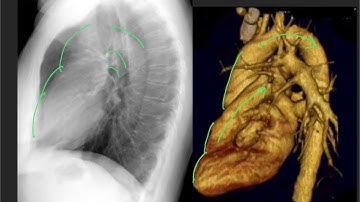

Lateral CXR Part 1 Anatomy - "EM in 5"